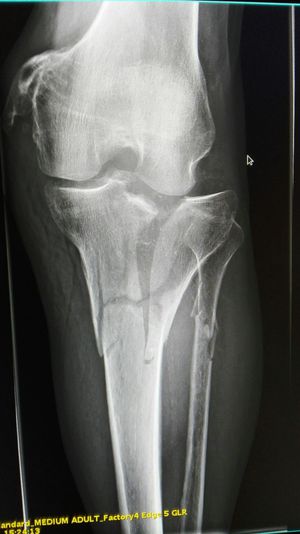

Fracture tibial plateau, schatzker classification, grade 6

Comminuted fracture of tibia